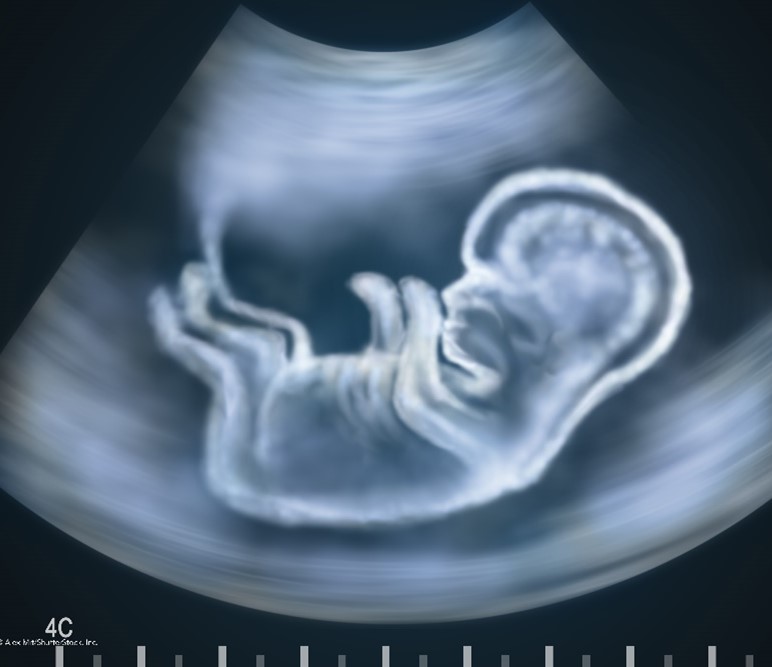

Ultrasound is a safe, noninvasive imaging modality that uses sound waves to generate images of internal body structures. Also referred to as sonography, ultrasound does not use x-rays or ionizing radiation and can be used for diagnostic and therapeutic indications. Ultrasound images are obtained by placing a small transducer (probe) and ultrasound gel on the skin. The transducer produces sound waves at very high frequencies, which exceed the threshold of human hearing. These high-frequency sound waves travel from the probe through the gel and into the body. The reflections of the sound waves off the structure being evaluated are used to generate images on a computer. Images are captured in real-time, which allows for evaluating the structures and movement of the body's internal organs, including blood flow through vessels. Transducers may be placed external to the body on the skin, such as with a transabdominal fetal ultrasound, which is demonstrated in Figure 6. Some transducers can also be placed directly inside the body via the vagina, GI tract, or blood vessels to optimize image quality. In these instances, a transducer is placed inside the vaginal canal of a nonpregnant female to enhance the visualization of the uterus and ovaries (FDA, 2020).

Figure 6

Fetal Ultrasound

Conventional ultrasound displays images in flat sections of the body. However, technological advancements have led to the development of an ultrasound that allows formatting sound wave data into 3-D images. The most widespread use of a 3-D ultrasound is to assess a developing fetus, and the distinction between the resultant images generated from a conventional sonogram versus a 3-D sonogram is demonstrated in Figure 7. A 4-D ultrasound can also be used to assess fetal characteristics. A 4-D ultrasound is a 3-D ultrasound that is put into motion (FDA, 2020).